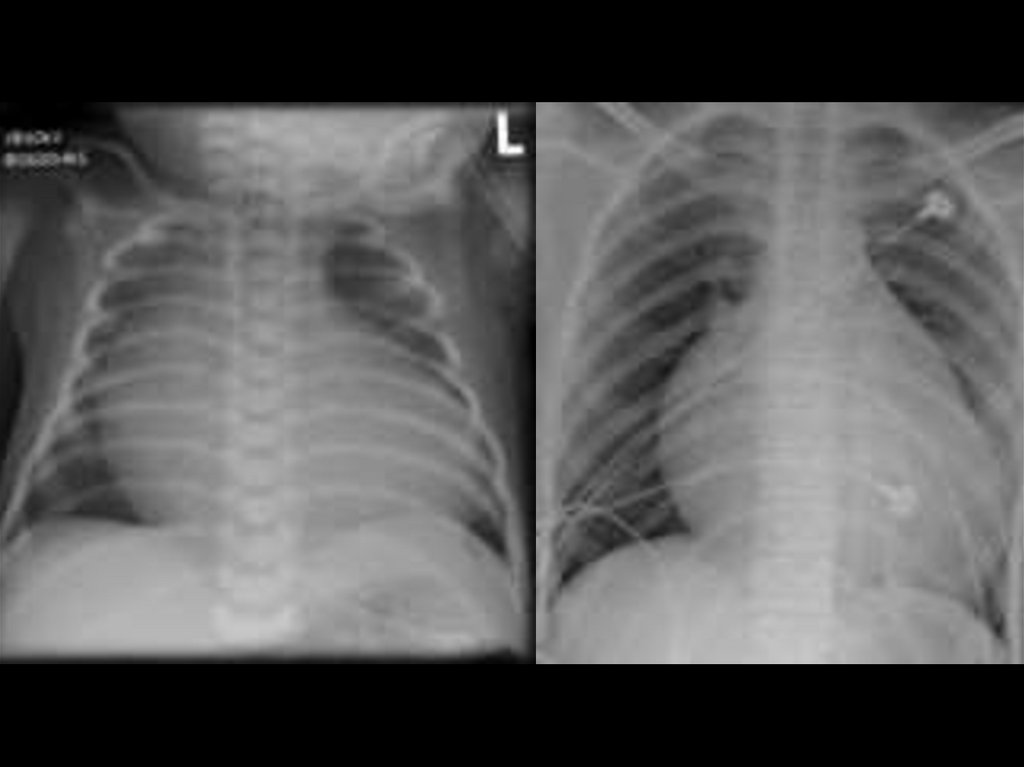

• Рентгенография грудной клетки: у новорожденных - кардиомегалия, которая может

быть массивной; легочная гипоплазия и олигемия; в легких случаях единственным

признаком

может

быть

легкая

или

умеренная

кардиомегалия.